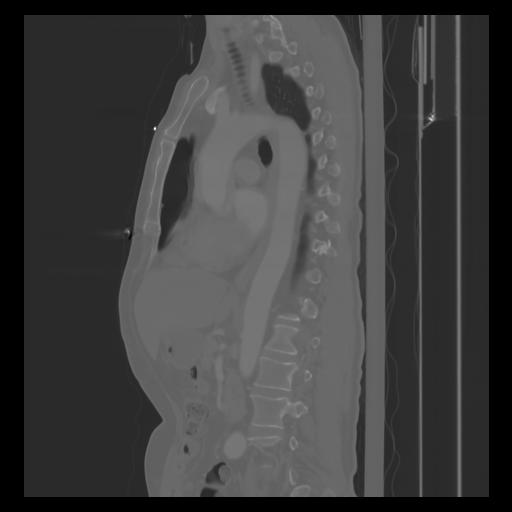

30 CUERPO,CE,Sagittal,3.000,CUERPO,Sagittal,